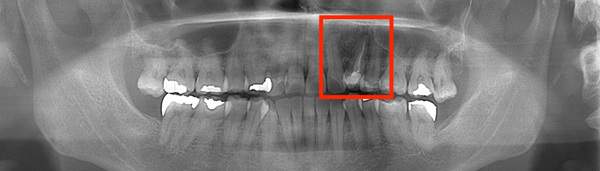

こちらは根の治療の経験がある歯ではありませんが、歯茎が大きく腫れていらした患者様です。レントゲンを撮ってみると原因となっていそうな、2本怪しい歯がありました。過去の虫歯の経緯から後ろの歯の方が怪しいと判断し、1本だけ治療を行いました。

治療後、腫れの大きさの確認のためにCTを撮影すると、上顎洞にまでおよぶ大きな炎症があり、骨が大きくなくなっていることが確認できました。

基礎に忠実に根の中をしっかり清掃し、防腐剤を詰めて経過をみるために3ヶ月後に再度CTを撮影しました。以前とは比べ物にならないくらい、上顎洞の炎症はなくなり。上顎洞を隔てる骨の再生もできました。 またこの治療で一番良かったのは、治療しなければならない歯とそうでない歯を鑑別できたことです。手前の歯はやはり治療する必要がなかったのです。

初診終了後にCT撮影です。上顎洞と歯が連続してしまうくらい炎症が広がっています。

根の先に黒い影があり、2本ともあやしいです。

きっちり清掃を行い防腐剤をつめました。

まだ根の先端に黒い影はあるが、治癒傾向にあると判断できます。